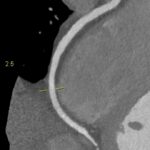

Figururile 1-9: reconstrucție în axul lung al vasului pentru arterele coronare cu evidențierea unui calibru global crescut la nivelul acestora și cu încărcătură ușoară-moderată de placă în principal calcificată

Discuţie caz nr 132: Examinările coroCT se efectuează în principal pentru aprecierea încărcăturii de placă precum și pentru evidențierea reducerilor de lumen ce necesită tratament. Această examinare a evidențiat creștere globală a calibrului arterelor coronare și o încărcătură ușoară-moderată cu placă în principal calcificată, fără a se evidenția arii de stenoză.